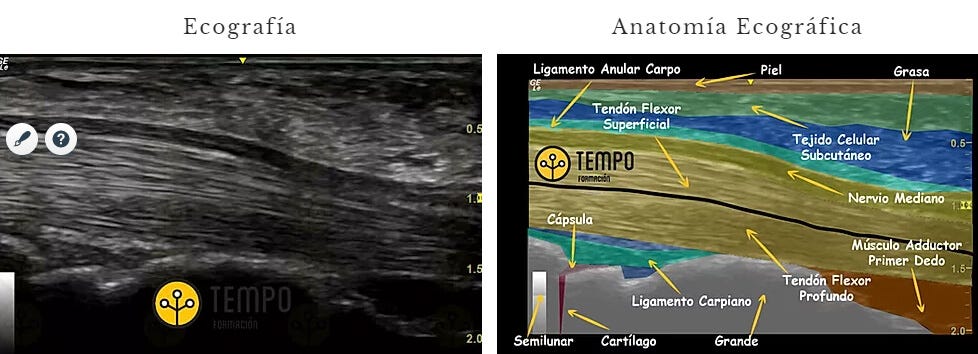

Isoecoico

"Es una estructura con un nivel de Gris similar a las estructuras periféricas."

Por ejemplo, en esta imagen del Corte Longitudinal del Nervio Mediano tienes a la izquierda la imagen ecográfica y a la derecha la anatomía ecográfica. A simple vista podría parecer que es todo una misma estructura pero si miras bien la imagen de la derecha comprobarás que hay mucho más de lo que pensábamos. Por eso es importante no sólo quedarte en un corte y hay que hacer barridos y pruebas dinámicas para comprobar y salir de dudas.